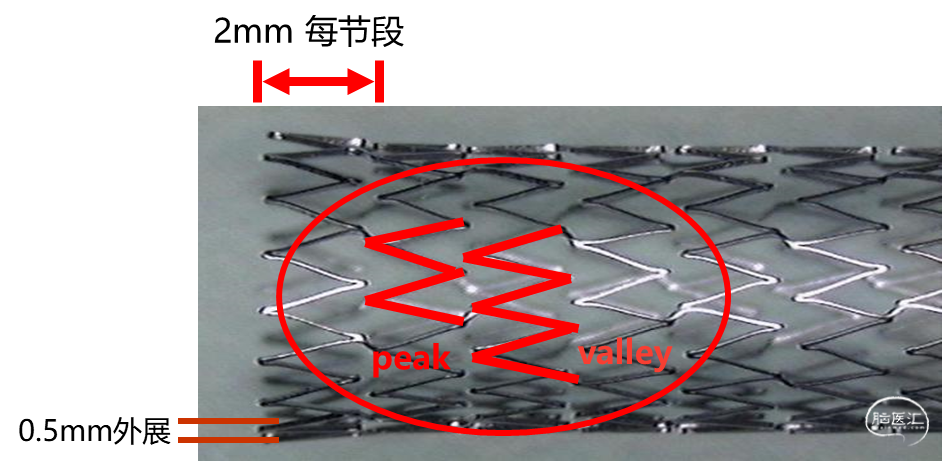

微网孔多节段设计,极佳的贴壁性和血管顺应性。

峰对谷设计,使支架弯曲时也能保持最大的柔顺性,无鱼鳞状突起,实现最佳贴壁,减小对血管产生的创伤。

支架边缘外展设计,能够精准定位迅速锚定,不易移位。